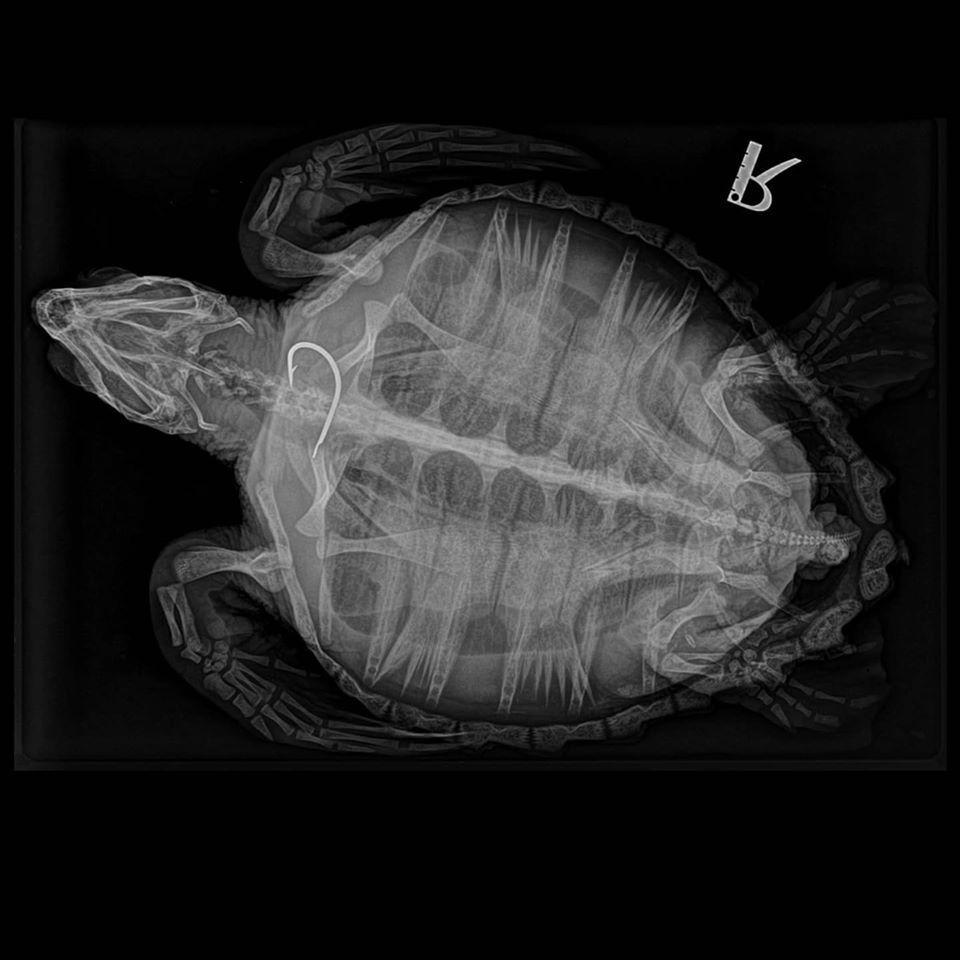

Intervienen en Palma a una tortuga marina para extraerle un anzuelo del esófago

Este anzuelo de la tortuga pertenece a un arte de pesca profesional (palangre) y NO a un pescador deportivo o aficionado!